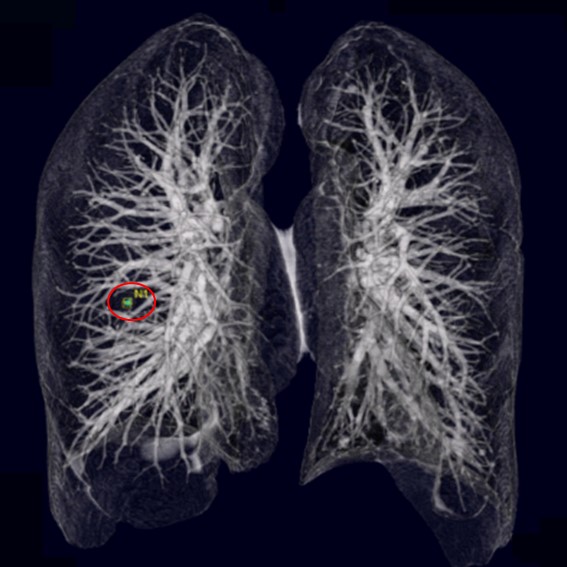

運用高科技尖端影像設備,提供貴賓精準的檢查、判讀、即時醫療、後續追蹤、健康管理或醫學中心轉介服務;從健檢診斷到後端治療,一條龍式服務。永越自成立以來,已服務超過16萬人次,每年通報件數超過千件,揪出包括:甲狀腺癌、肝腫瘤、肺癌、乳癌、子宮頸癌等重大異常的健康警訊,把握住早發現早治療的黃金關鍵。